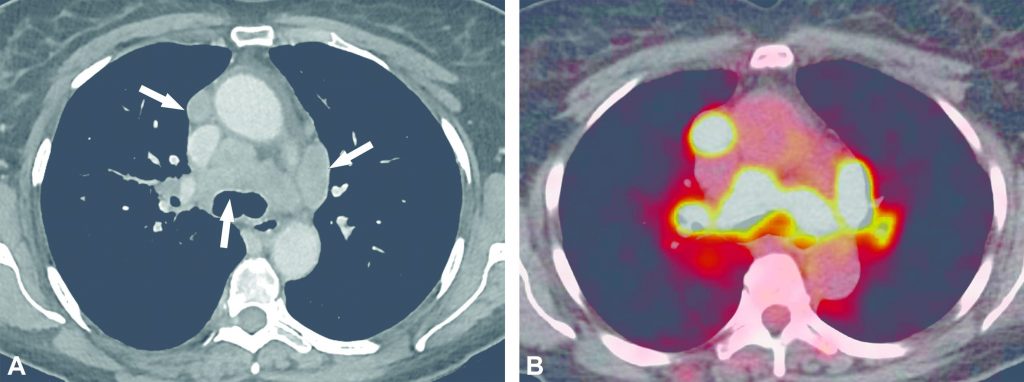

C. TEP-TDM au 18FDG

La TEP-TDM au 18FDG montre des hypermétabolismes reflétant l’intensité et l’évolution de l’activité inflammatoire de la maladie (figures 99.6 à 99.8).

Fig. 99.6. Scanner thoracique injecté et TEP-TDM au 18FDG réalisé dans le cadre d’une sarcoïdose ganglionnaire à la recherche de cibles biopsiables.

Le scanner montre des adénomégalies médiastinales bilatérales et symétriques (flèches en A) qui sont hypermétaboliques sur l’imagerie de fusion TEP-TDM (B). Ceci est en faveur d’une activité de la maladie.

Source : CERF, CNEBMN, 2022.